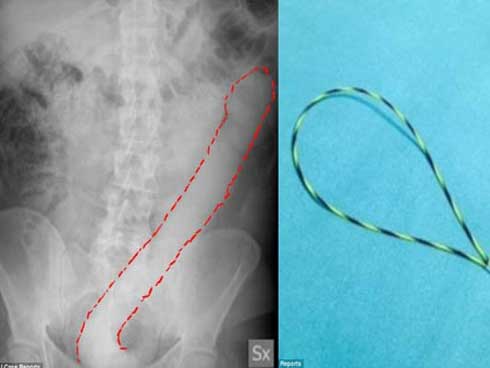

Ở dương vật bình thường, khi cương cứng sẽ thẳng. Nếu mô sẹo tích tụ không đều trên thân dương vật, dương vật của các quý ông có thể bị cong, xảy ra phổ biến nhất ở tuổi trung niên. Các mảng xơ hoặc cục xơ cứng phát triển giữa hai lớp áo của tổ chức cương ở dương vật (vật hang) gây co kéo và dính chắc làm cho dương vật cong và biến dạng khi cương lên.

Khi mảng xơ phát triển ở mặt lưng dương vật sẽ làm cho dương vật cong gấp khúc lên trên, còn khi nó phát triển ở mặt bụng của dương vật sẽ làm cho cậu bé cong gấp khúc xuống dưới. Cũng có thể mảng xơ nằm ở cả hai mặt làm cho dương vật lồi lõm và ngắn lại. Khi ấy, bệnh có thể gây ra sự đau đớn khi cương cứng và làm cho việc quan hệ tình dục khó khăn. Những trường hợp này cần đi khám chuyên khoa để yêu cầu phẫu thuật chỉnh sửa lại hình dáng dương vật.